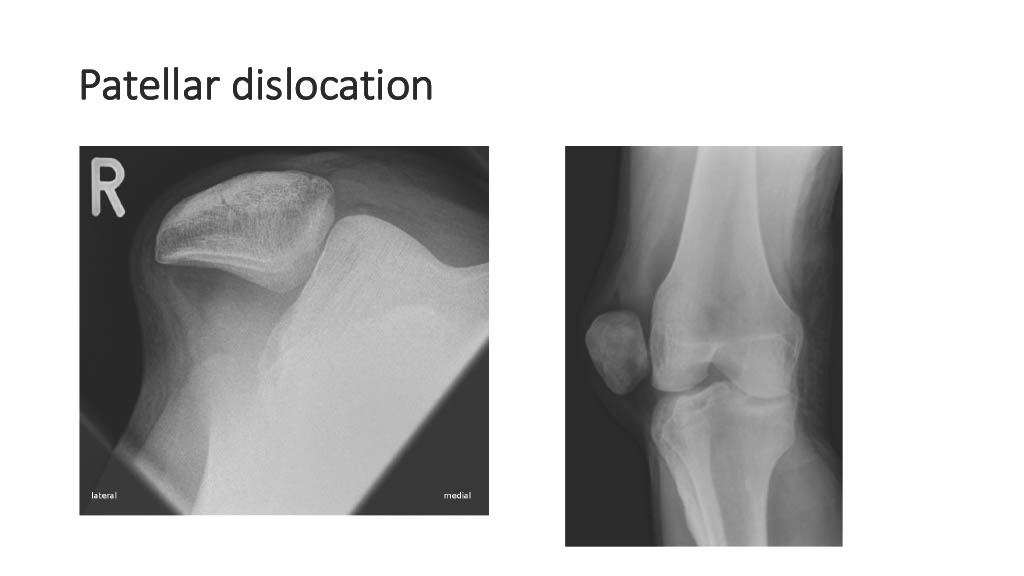

Vogrin, Matjaž, MD, PhD.

Department of Orthopaedics & Sports Medicine Institute, University Medical Centre Maribor, Slovenia

“Surgical treatment of knee injuries in skiing”

Prof. Matjaž Vogrin is an orthopaedic surgeon and specialist in arthroscopic surgery and sports injuries. He is chairman of the Institute of Sports Medicine ” at the Faculty of Medicine in Maribor, Slovenia, and head of the medical subdivision of the Slovenian National Olympic Committee.

He was chief physician of the Slovenian Olympic team at the 2012, 2016, 2021 and 2024 Olympic Games (London, Rio, Tokyo, Paris), official physician of the Slovenian national football team and head of the Slovenian medical team at the 2010 FIFA World Cup in South Africa. He has also been head of the medical team of FC Maribor ( UEFA Champions League and Europa League participants) since 1999. He has been an invited speaker at sports medicine congresses and conferences worldwide.

Surgical treatment of knee injuries in skiing